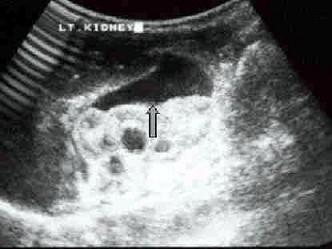

图中标记处为 ?(?)A.腹腔积液B.肾周积液C.肠管内液体D.肾结核E.以上都不是

问题 图中标记处为 ?(?)

选项 A.腹腔积液 B.肾周积液 C.肠管内液体 D.肾结核 E.以上都不是

答案 B